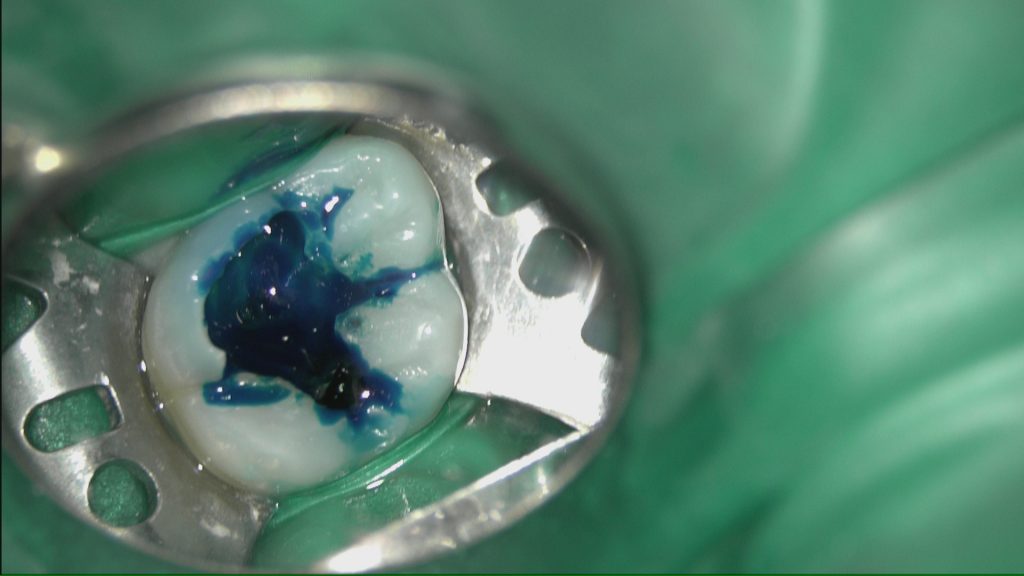

う蝕検知液を使いカリエスを慎重に除去していきます。

虫歯の取り残しは問題外です(^^;)